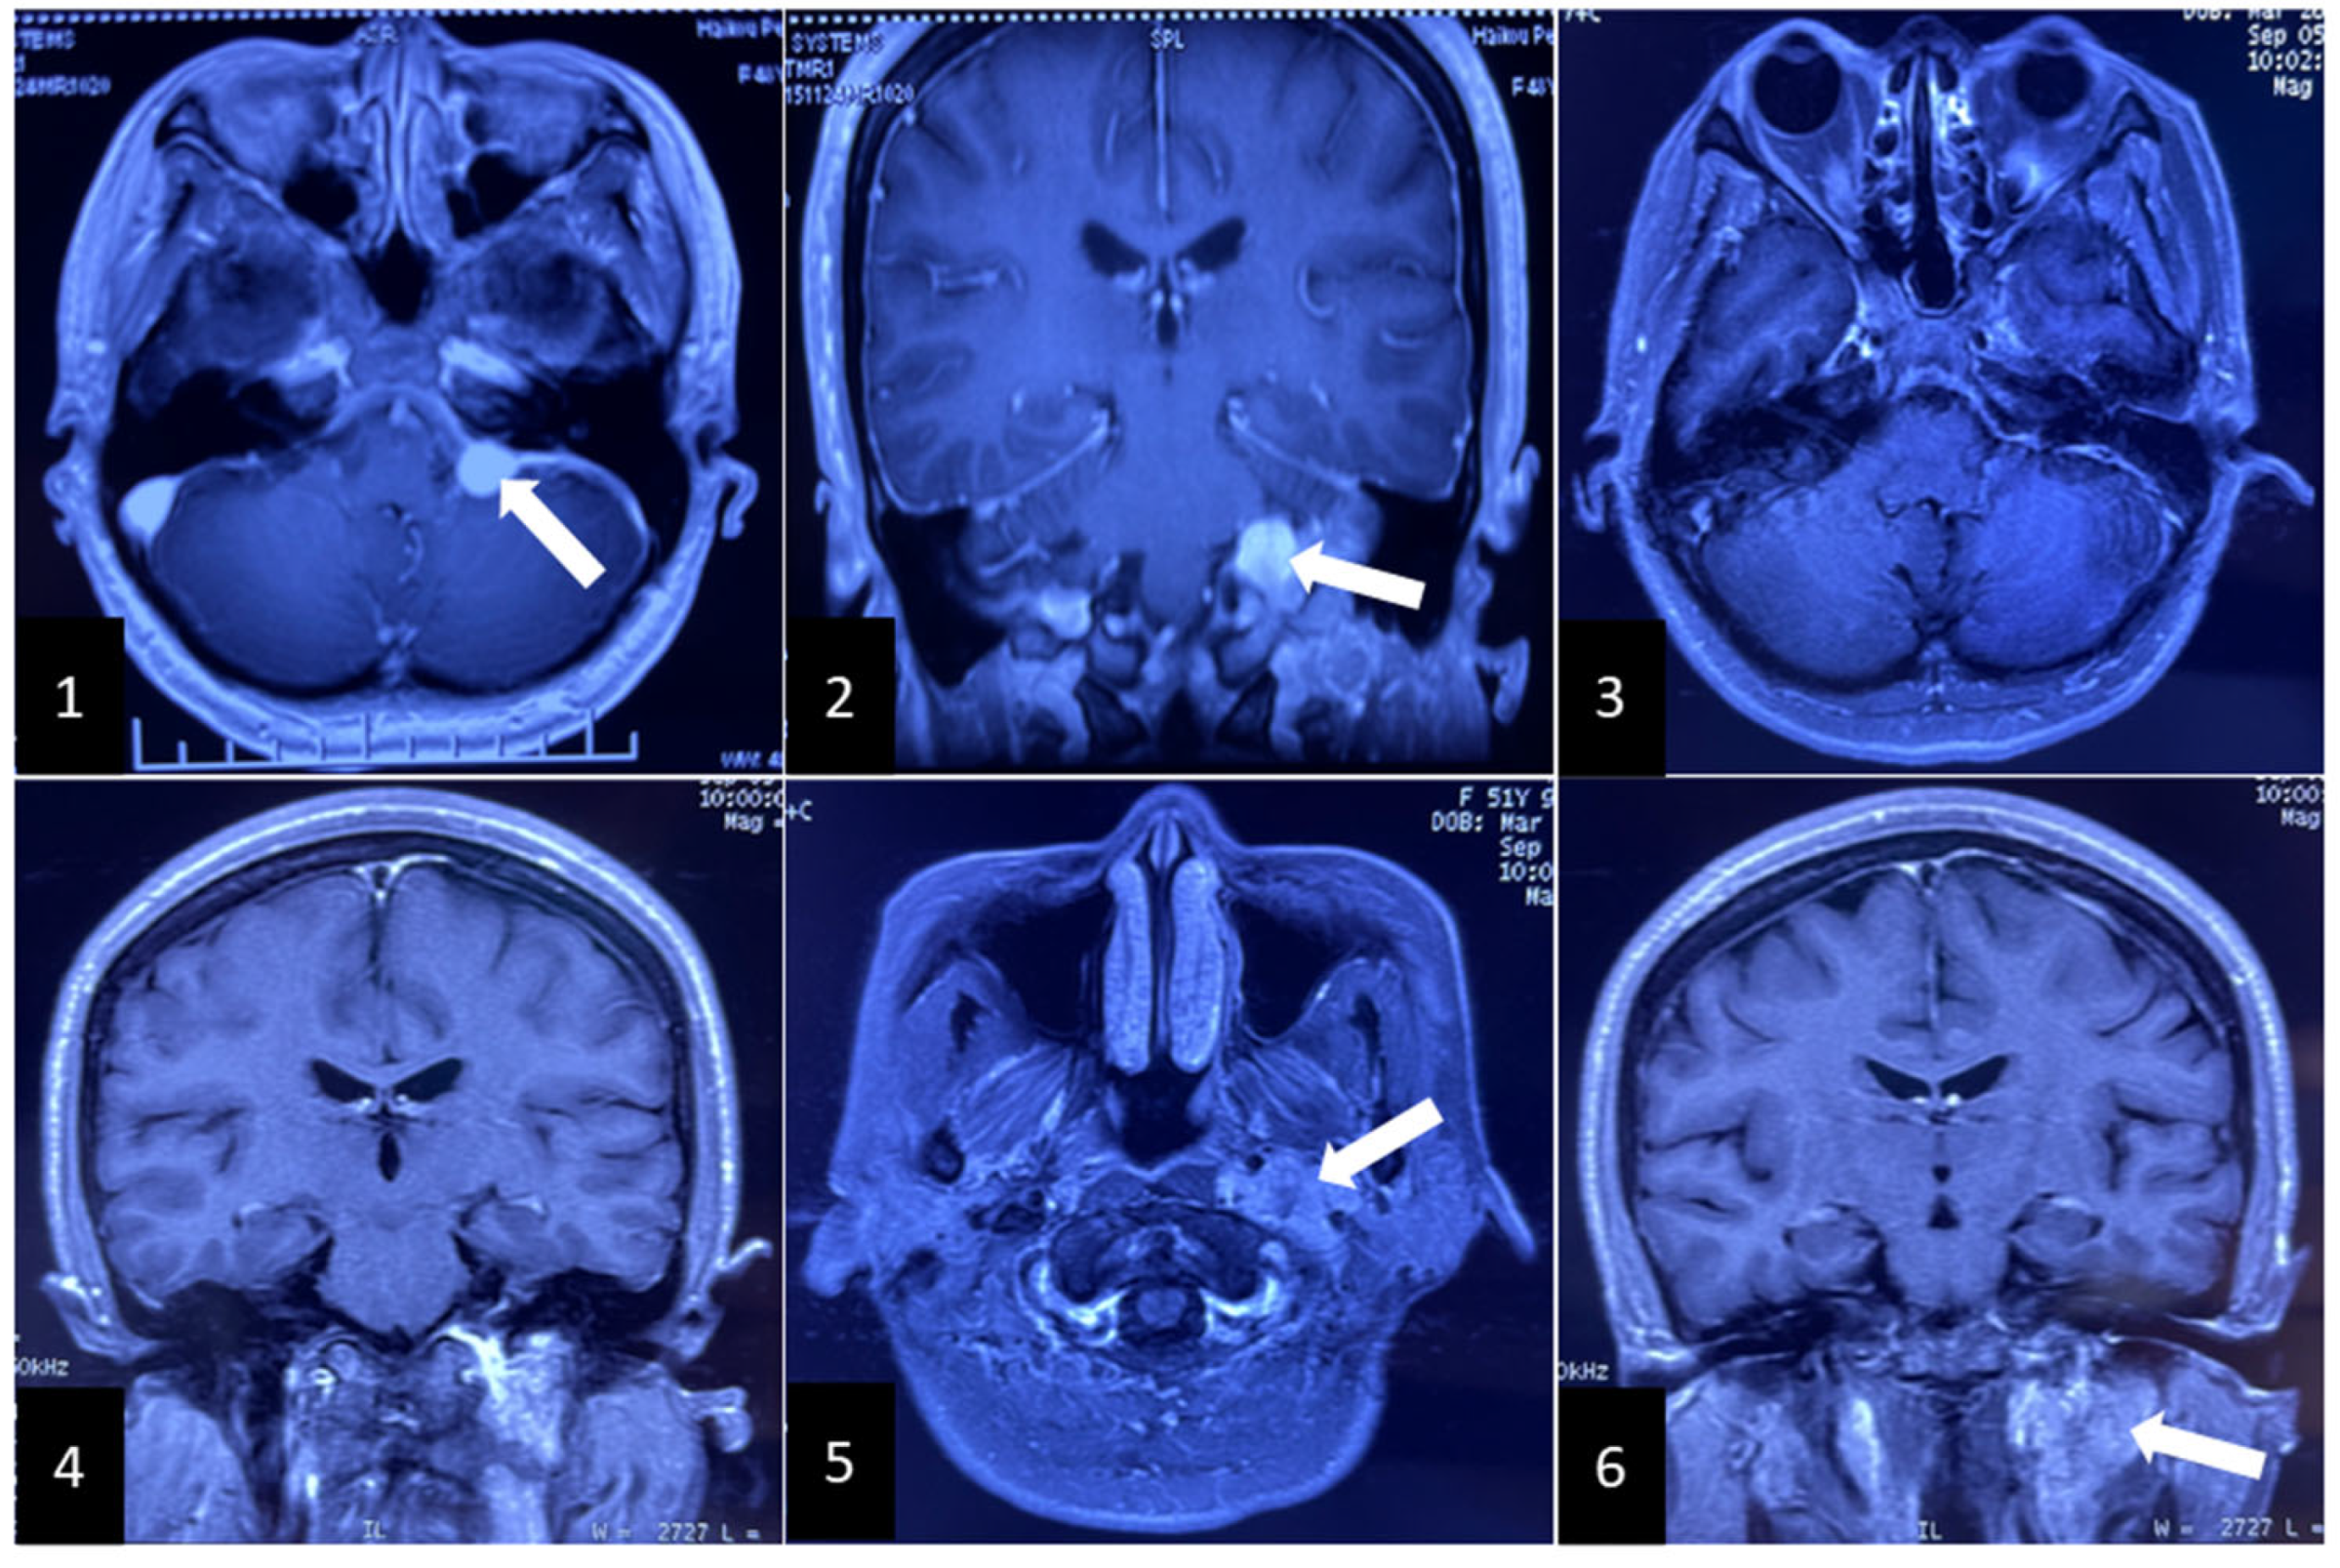

2. Clinical Case